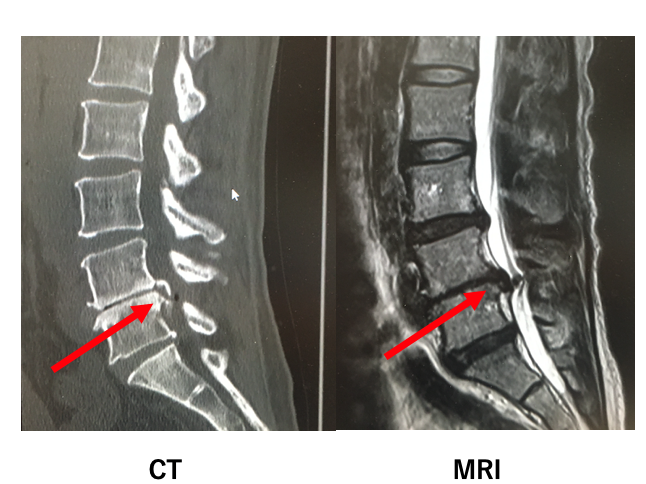

「後縦靭帯骨化症」

後縦靭帯骨化症(OPLL)は、脊椎をつなぐ後縦靭帯が骨化する疾患で、

特に頸椎に多く見られます。

この病気は、脊椎の後縦靭帯が骨化することで神経を圧迫し、

様々な神経症状を引き起こす可能性があります。